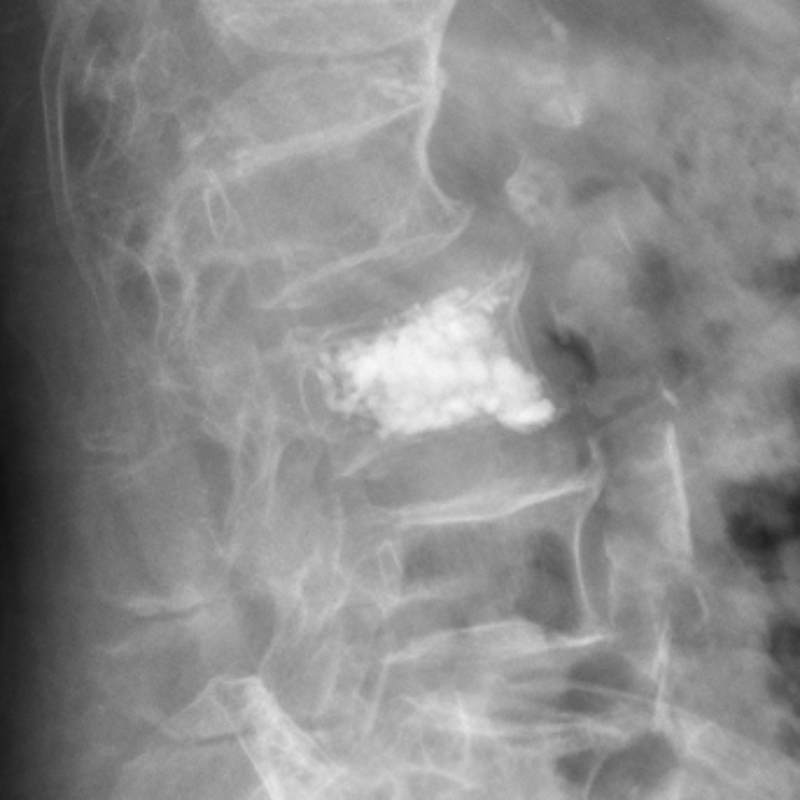

△術后復查胸6、腰3椎體內骨水泥置入狀態良好。